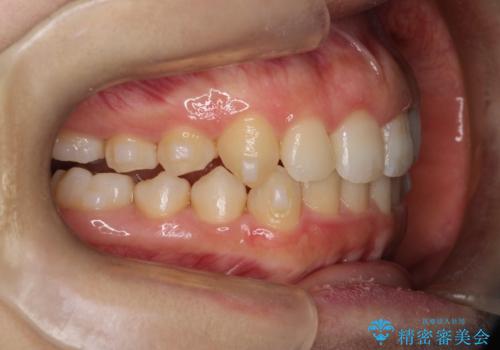

押しつぶされた歯列、アーチの拡大だけで非抜歯で改善した症例

初診時の歯並びの状態としては、上下ともに全体に及ぶの中等度以上のがたつき(叢生)があり、全額的に歯列のアーチが内側に押しつぶされた状態でした。

強い叢生がありましたが、抜歯は行わず上下顎ともに、主に歯列弓の拡大を行い叢生を改善しました。